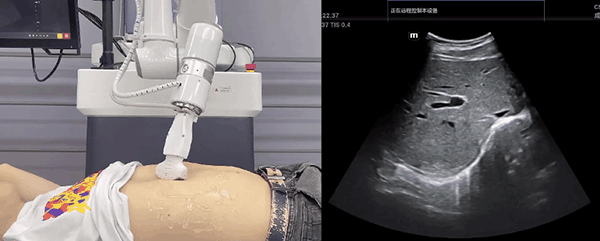

G22恒峰机器人末端搭载超声探头,可以对浅表小器官和外周血管、腹部(肝、胆、胰、肾等器官)进行超声检查。

目前,G22恒峰机器人在生物医药、医疗健康领域的赋能已有显著进展,G22恒峰协作机器人应用场景覆盖了临床试验、试管检测、拭子采集、试管搬运、荧光检测、康复治疗、超声扫查、导诊、消毒、微创治疗、针灸刮痧等。